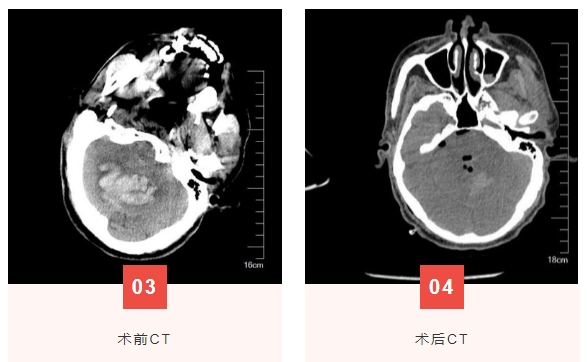

陈大爷因“头痛伴意识障碍3小时”急诊入院 。入院时神志模糊,双肺呼吸音粗糙,四肢肌力3级,肌张力不高,指鼻试验不配合。急诊头颅CT提示小脑血肿破入脑室,量约20毫升。询问患者家属得知陈大爷既往有冠心病、心律失常等病史,入院初步诊断为高血压性脑出血、小脑出血破入脑室、高血压病3级(极高危)。

高血压性脑出血是致死、致残率极高的疾病,严重危害人民群众健康,好发于基底节区、丘脑、脑室及小脑等部位,治疗主要方式有开颅显微镜下血肿清除术、钻孔穿刺引流术、神经内镜辅助微创血肿清除术。考虑患者年龄大、心肺功能差,常规开颅血肿清除术患者难以耐受,且手术面临极大挑战。患者病情紧急,为抢救患者生命,神经外科副主任黄锦峰和主管医师王新瑜积极完善术前准备和沟通,决定采用神经内镜微创手术清除小脑血肿。在麻醉团队紧密配合下,手术顺利完成。术后患者神志清楚,四肢肌力恢复,三周后患者顺利出院。